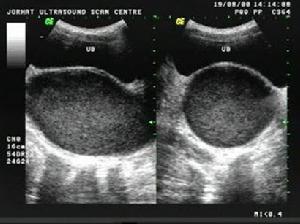

處女膜閉鎖絕大多數處女膜閉鎖患者臨床上表現為青春期後出現逐漸加劇的周期性下腹痛,但無月經來潮。嚴重者伴有便秘、肛門墜脹、尿頻或尿瀦留等症狀。檢查時見處女膜向外膨隆,表面呈紫藍色,無陰道開口。當用示指放人肛門內,可捫到陰道內有球狀包塊向直腸前壁突出。行直腸一腹部診時可在下腹部捫及位於陰道包塊上方的另一較小包塊(為經血瀦留的子宮),壓痛明顯。如用手往下按壓此包塊時,可見處女膜向外膨隆更明顯。盆腔B型超聲檢查可發現子宮及陰道內有積液。確診後應立即手術治療。先用粗針穿刺處女膜正中膨隆部,抽出褐色積血證實診斷後,即將處女膜作;形切開,引流積血。積血大部排出後,常規檢查宮頸是否正常,但不宜進一步探查宮腔以免引起上行性感染。吸盡積血後,切除多餘的處女膜,使切口呈圓形,再用3―0可吸收縫線縫合切口邊緣黏膜,以保持引流通暢和防止創緣粘連。術後留置導尿管1-2日,外陰部置消毒會陰墊,每日擦洗外陰1―2次直至積血排淨為止。術後給予抗感染藥物。

輔助檢查:C 盆腔的CT檢查 B 腹腔鏡 A 婦產科的超聲檢查 A 尿常規檢查 A 血液常規檢查